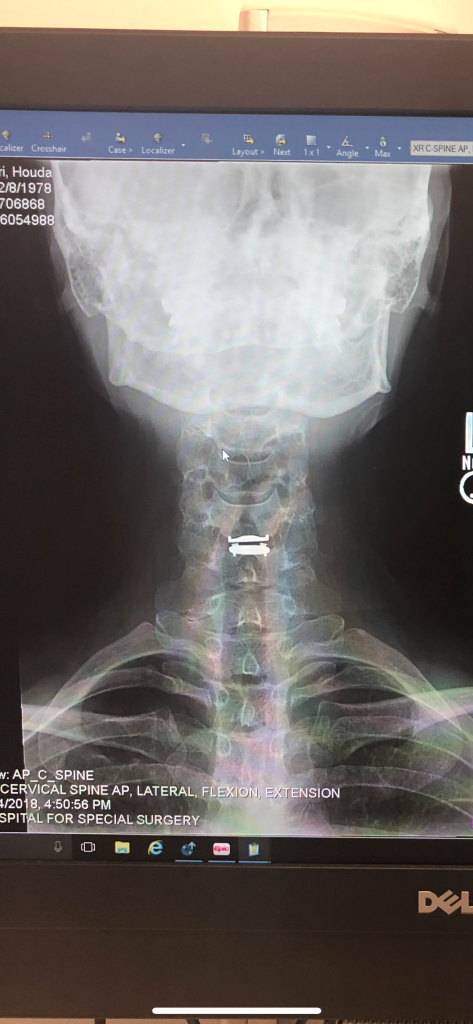

Dr. Huang gave me my life back! I was diagnosed with a C5-C6 disk herniation 2 years ago which would cause extreme pain from my neck down to my whole left side shoulder and arm. I tried everything to treat it from physical therapy to acupuncture to epidurals and medication (nerve pain and muscle relaxers). The pain was debilitating. I was finally told by Dr. Robert Griffin at HSS that I should consider surgery. He recommended 3 surgeons to me and Dr. Huang was one of them. After doing my research I chose to go with Dr. Huang. The staff at the HSS Integrative Center (where I was getting my PT) all spoke very highly of Dr. Huang and told me if went with him, I was in good hands. What I appreciated about Dr. Huang is that he first reviews your medical file, MRIs and x-rays before meeting with you to decide if you are a good candidate for surgery. From the initial consultation appointment I felt so at ease and comfortable with him. He went over all my MRI images with me and patiently explained what the images revealed and which surgery options were available in my case. I asked Dr. Huang many questions, which he answered thoughtfully. I never felt rushed. He thoroughly explained the procedure, expectations and risks as well. He was very cordial and calming at the end of the visit. It took me a couple of days to decide I was going to proceed with the surgery with Dr. Huang and I’m so happy I did! I had my surgery 11 weeks ago and I feel great! Dr. Huang performed a total disc replacement at C5–C6. Recovery was not so bad at all. His staff is excellent. HSS is a great hospital. I can finally live pain free! Thank you so much Dr. Huang!!!